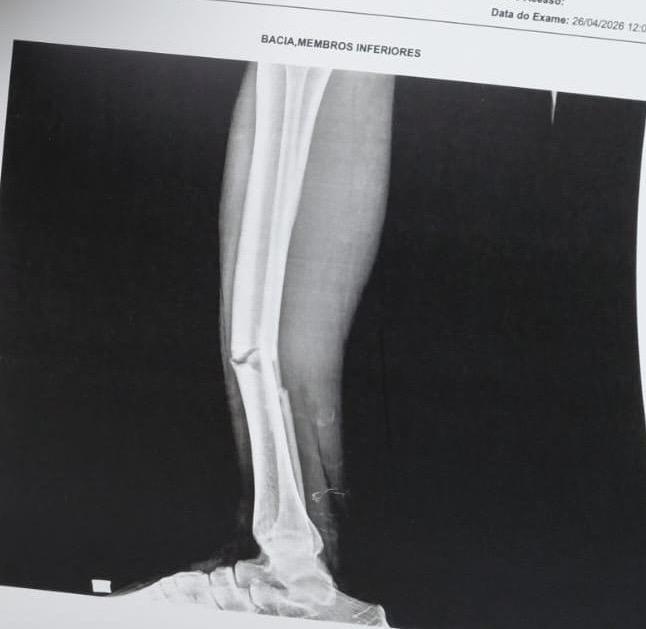

Socorristas do SAMU foram acionados e encaminharam o homem de 50 anos para atendimento hospitalar. Uma imagem de Raio X mostra como ficou a perna do jogador, que agora passa a se recuperar após o ocorrido.